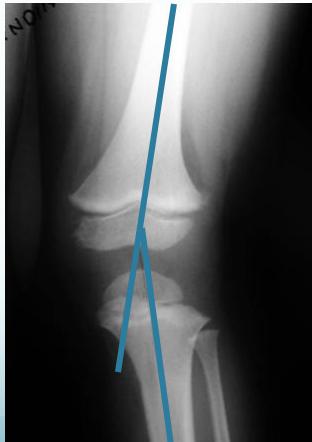

Radiological Assessment

Indications: X-ray when severe or possibly pathologic

Recommended Views:

- Standing AP film: Long film (hips to ankles) with patellae directed forwards

Radiological Parameters to Assess:

- Medial Physeal Slope

- Femoral-Tibial Axis

Angle measurements

Medial Physeal Slope

Femoral-Tibial Axis